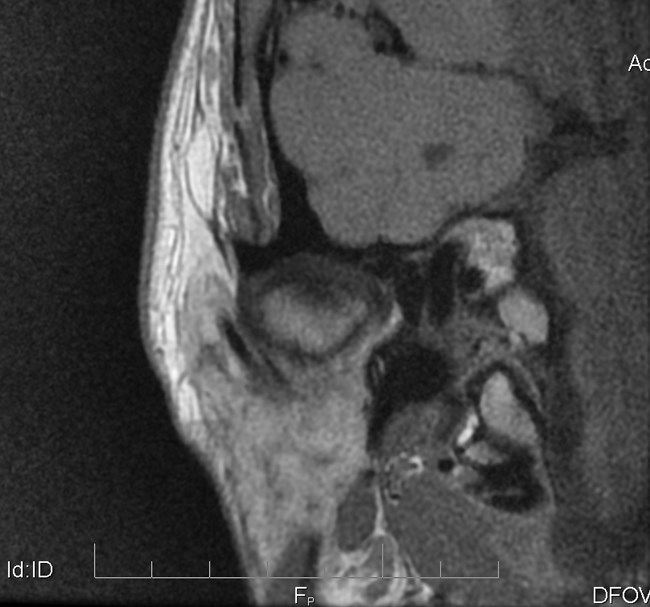

Na podstawie uzyskanych wyników badań zastosowano repozycyjną szynę zgryzową oraz terapię manualną narządu żucia. Po trzymiesięcznym leczeniu uzyskano poprawę modelu ruchomości żuchwy. W związku z utrzymywaniem się silnych dolegliwości bólowych zlecono dodatkowo badanie tomografii rezonansu magnetycznego (MR), w którym w zwarciu stwierdzono obustronne doprzednie przemieszczenie krążków stawowych (ryc. 5). W zwarciu na przekrojach czołowych widoczne było spłaszczenie powierzchni stawowej lewego ssż (ryc. 6). W rozwarciu pozycja obydwu głów żuchwy była doprzednia w stosunku do szczytów guzków stawowych, a nad głowami żuchwy leżały pasma przednie krążków stawowych. Przemieszczenie głowy żuchwy było bardziej nasilone w prawym stawie skroniowo-żuchwowym (ryc. 7).

Ryc. 5a i 5b. Przekroje strzałkowe MR ssż w zwarciu, obrazy PD-zależne. Doprzednie przemieszczenie krążków w prawym (a) i lewym (b) ssż.